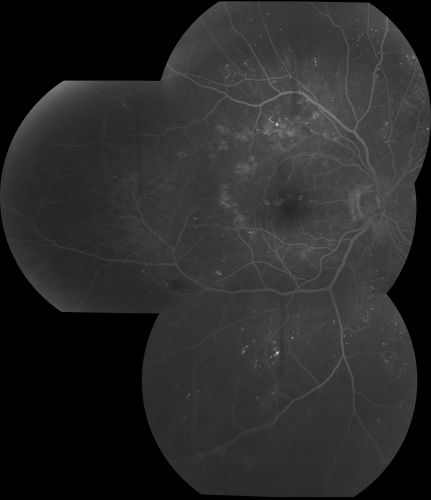

Diabetic Macular Edema

63 yr old Male

VA 20/20 OD 20/25 OS

No complaints